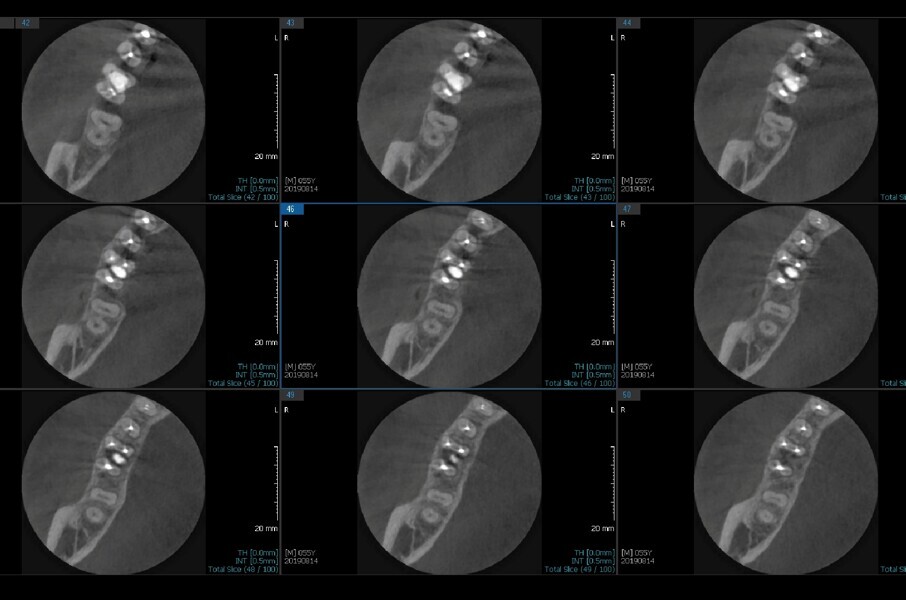

Fig.2a: Pre-op CBCT images of tooth #46: No obturation material in the distal and mesiobuccal canal (a); scanty obturation of the canals and breach of the floor of the pulp chamber, no obturation beyond a few millimetres down the orifice (b & c); radiolucency in the furcation area and periapical region of both roots (d -g).

Fig.2b: Pre-op CBCT images of tooth #46: No obturation material in the distal and mesiobuccal canal (a); scanty obturation of the canals and breach of the floor of the pulp chamber, no obturation beyond a few millimetres down the orifice (b & c); radiolucency in the furcation area and periapical region of both roots (d -g).

Fig.2c: Pre-op CBCT images of tooth #46: No obturation material in the distal and mesiobuccal canal (a); scanty obturation of the canals and breach of the floor of the pulp chamber, no obturation beyond a few millimetres down the orifice (b & c); radiolucency in the furcation area and periapical region of both roots (d -g).

Fig.2d: Pre-op CBCT images of tooth #46: No obturation material in the distal and mesiobuccal canal (a); scanty obturation of the canals and breach of the floor of the pulp chamber, no obturation beyond a few millimetres down the orifice (b & c); radiolucency in the furcation area and periapical region of both roots (d -g).

Fig.2e: Pre-op CBCT images of tooth #46: No obturation material in the distal and mesiobuccal canal (a); scanty obturation of the canals and breach of the floor of the pulp chamber, no obturation beyond a few millimetres down the orifice (b & c); radiolucency in the furcation area and periapical region of both roots (d -g).

Fig.2f: Pre-op CBCT images of tooth #46: No obturation material in the distal and mesiobuccal canal (a); scanty obturation of the canals and breach of the floor of the pulp chamber, no obturation beyond a few millimetres down the orifice (b & c); radiolucency in the furcation area and periapical region of both roots (d -g).

Fig.2g: Pre-op CBCT images of tooth #46: No obturation material in the distal and mesiobuccal canal (a); scanty obturation of the canals and breach of the floor of the pulp chamber, no obturation beyond a few millimetres down the orifice (b & c); radiolucency in the furcation area and periapical region of both roots (d -g).